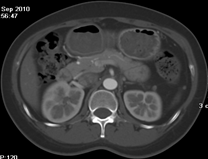

如上圖所示,相鄰的三張軸位圖像未見明顯異常,根據傳統軸位圖像很難得到準確的臨床診斷。

同一病人利用容積數據進行三維處理后,高品質MPR和三維圖像上則清晰顯示了縱向排列的腹腔干與腸系膜上動脈相鄰近,血管發生變 異,近端血管閉塞,為臨床提供了精確的診斷信息。